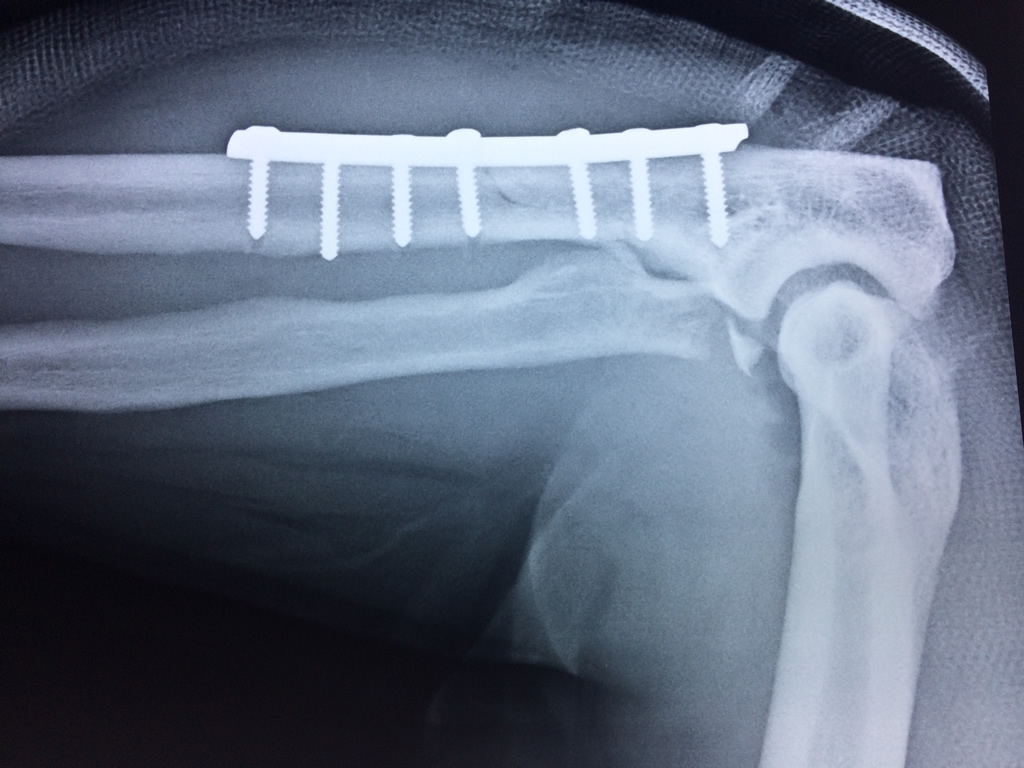

Cirugías de Hombros - Codo